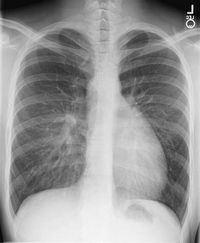

흉부 엑스레이 검사에서 대혈관 전위는 일반적으로 "실에 매달린 달걀"처럼 보이는 심장-종격동 윤곽을 보여준다. 심장 비대는 옆으로 누인 달걀을 나타내고, 상부 종격동의 좁아진 위축된 흉선은 실을 나타낸다.[4]